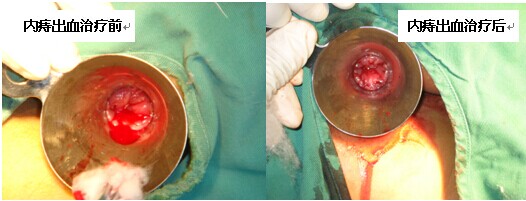

痔疮治疗的先进理念——痔疮铜离子电化学治疗技术

该项治疗技术是将铜质电极刺入痔及其支持组织中,通过铜离子及电化学方式引起血管壁上皮细胞水肿和微血栓形成,导致无菌性炎症、组织机化、血管闭塞以及促进周围组织纤维化从而达到消除粘膜下层血管出血性病变以及痔脱出。